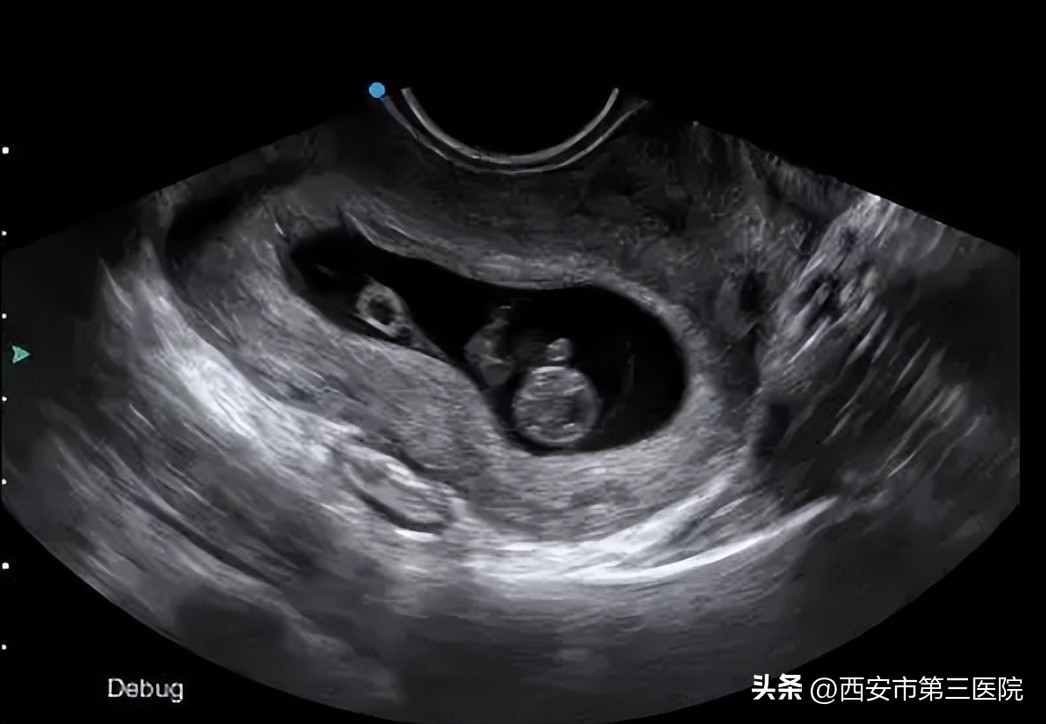

阴超相比腹超来说,阴超会看得更清楚。尤其是看早孕,阴超更合适。阴超相较于腹超来说,可以更早地发现宫内妊娠,能更早的看到胚胎着床位置、孕囊、卵黄囊、胎芽胎心。因为阴道很接近卵巢和子宫,所以可以很清晰的看见子宫和卵巢的情况以及子宫内胚胎发育的发育情况。